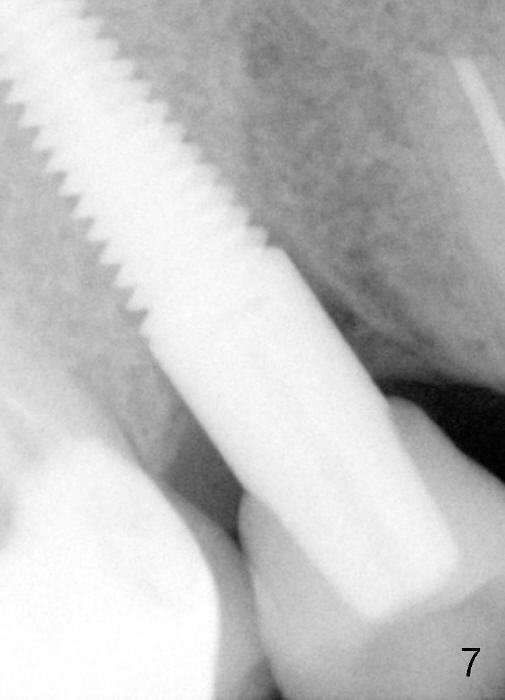

Fig.7: Six months post cementation. The difference is probably due to different angulation when X-ray is taken.